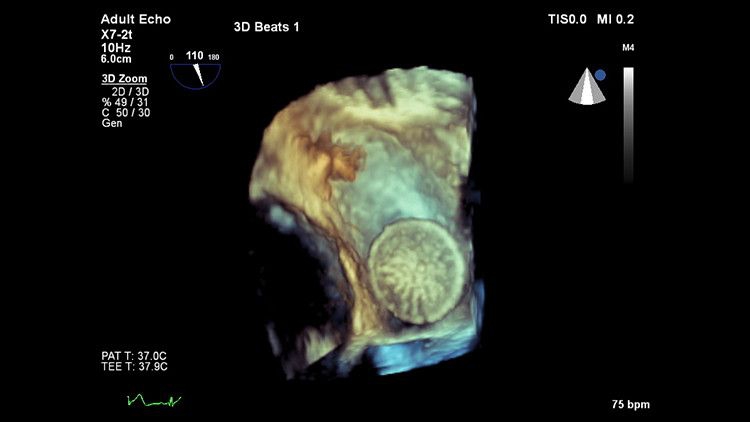

Ультразвуковая система Philips EPIQ CVx предоставляет врачу широкий спектр возможностей для еще более качественной и точной визуализации. Благодаря высокому разрешению дисплея, система обеспечивает максимальную детализацию как в 2D, так и в 3D режимах, а также при доплеровском картировании.

Ультразвуковая система Philips EPIQ CVx предоставляет врачу широкие возможности для еще более качественной и точной визуализации. Благодаря высокому разрешению дисплея, система обеспечивает максимальную детализацию как в 2D, так и в 3D режимах, а также при доплеровском картировании. Технологии Philips позволяют специалистам расположить УЗ-снимок на всей диагонали экрана в режиме реального времени без потери качества.

Система EPIQ CVx представляет собой специализированное решение для ультразвуковых исследований сердца, которое значительно улучшает функциональные возможности. Это способствует повышению качества медицинской помощи путем увеличения вычислительной мощности, обеспечения исключительного качества визуализации с более высокой четкостью и резкостью, повышения эффективности исследований, а также использования новой технологии надежного и воспроизводимого количественного анализа данных AIUS.

Качество изображения на EPIQ CVx

Монитор с технологией OLED обеспечивает четкую визуализацию анатомии сердца за счет расширенного динамического диапазона и улучшенного контраста. Каждый может увидеть изображение с высокой четкостью даже в нетрадиционных условиях, таких как операционная.